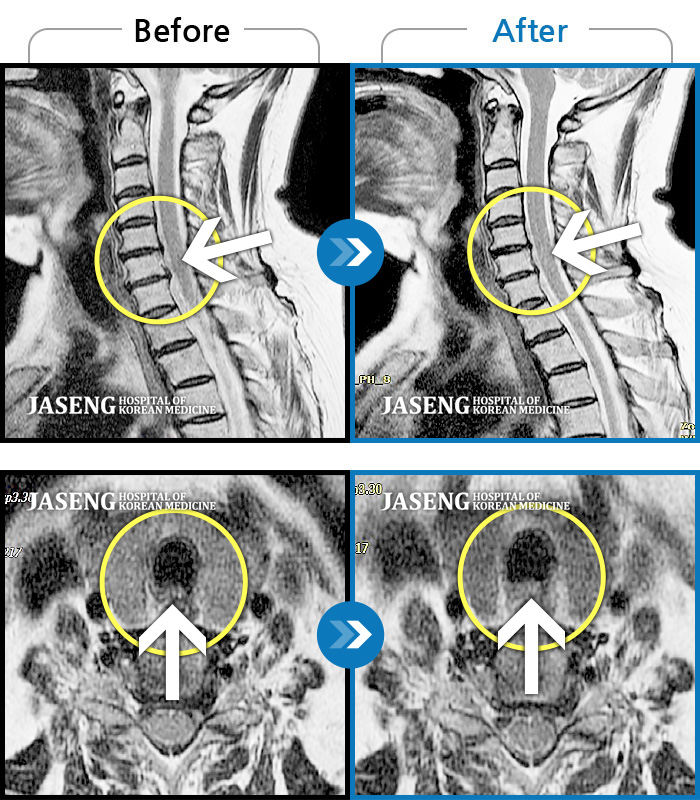

목디스크

도움받은 사례

인천 · 강아현 원장

처음 내원시 목에서 등으로 이어지는 통증 및 우측 팔 저림 증상이 심했고, 약간의 근력저하도 동반되어 일상생활이 어려운 상태였습니다.

촬영시기

2024.04.06 ~ 2024.11.16

2024.11.22

조회수 17,045